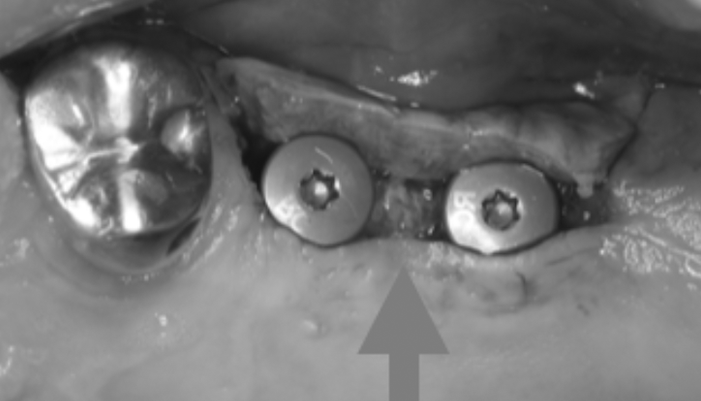

治療前

患者様は「インプラントした部分を長く安心して使える状態にしたい」とのご希望で来院されました。初診時は、すでにインプラントが埋入されており二次手術前の状態でしたが、角化歯肉の幅が不足しており、将来的な清掃性や安定性に不安がある状態でした。そこで、単純な二次手術のみではなく、インプラント周囲に十分な角化歯肉を確保する処置を併用し、清掃しやすく長期的に安定しやすい環境を整えました。

| 主訴 | インプラント治療の続き。 |

|---|---|

| 治療期間 | 1回 |

| 治療費 | ¥33,000(税込) |

| 治療内容 | インプラントの2次手術として歯肉形成を行いました。硬いしっかりした歯茎(角化歯肉)がないと将来的にインプラントが炎症を起こしやすいためです。 |

| 治療のリスク | 腫れ・出血などが生じる場合があります。 |